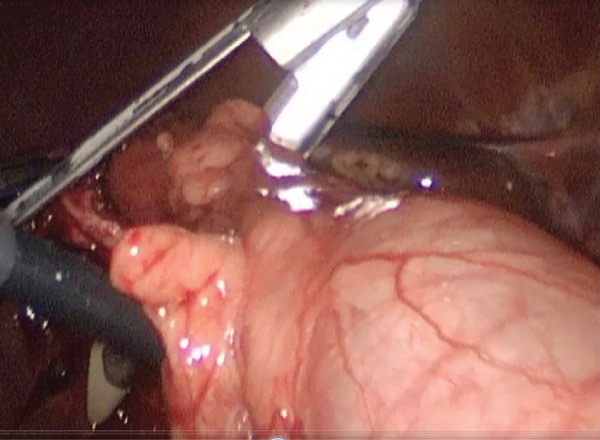

At any rate, the key to success with the procedure is that it’s performed properly.

“It cannot be just like a fundectomy or a partial cholecystectomy,” Dr. Roch explained. “And remember that it’s perfectly fine to do a reconstituting subtotal, as long as you need to extract all the stones before closing your remnant. Finally, your remnant needs to be small. It cannot be a 7-cm remnant—that’s called a gallbladder.”

Although Dr. Telem acknowledged that it’s easy to be a “Monday-morning quarterback,” she said some of the videos she’s seen on various websites and YouTube have made her question some of the situations in which surgeons chose to perform a subtotal cholecystectomy.

“It certainly looks, at least to the trained eye, that something else could have been done and there’s a lot of gallbladder being left in place,” she said. “It almost makes me wonder what the repeat cholecystectomy rate is going to be in these patients.”